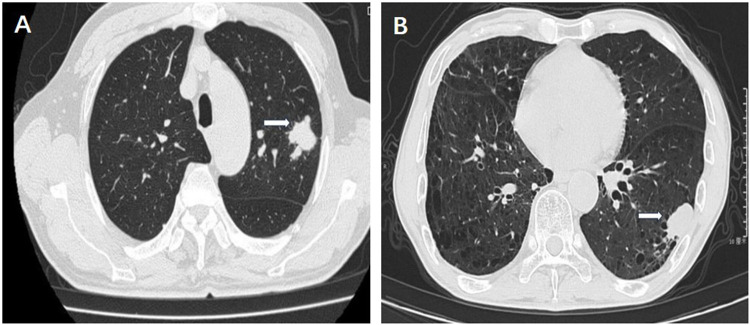

Results: Among the seven cases of SMARCA2-deficient lung adenocarcinoma, five were male and two were female, with an average age of 68.7 years. Four patients had a smoking history averaging 35 years, all seven patients exhibited respiratory symptoms. Histologically, these tumors displayed diverse features, including rhabdoid morphology, giant cells, and necrotic areas. The tumor cells exhibited eosinophilic cytoplasm, large nuclei with prominent nucleoli. Immunohistochemically, the tumor cells revealed SMARCA2 negativity with SMARCA4 expression. P53 staining revealed diffuse strong nuclear expression in 5 cases and complete absence expression in 2 cases. β-catenin expression was partially abnormal in 3 cases, with positive nuclear and cytoplasmic staining. PD-L1 expression was detected as positive in 5 cases. Next-generation sequencing identified mutations in driver genes KRAS, MET, and EGFR in 4 cases, and TP53 mutations in 7 cases. Clinical follow-up revealed that 2 patients died of tumor progression, 5 patients achieved complete response within a follow-up period of 10 to 33 months (median = 18.3 m).